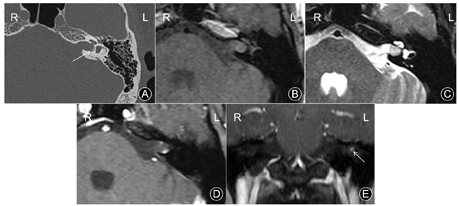

影像学检查:CT平扫示左侧IAC开口轻度膨胀伴软组织病灶,IAC后壁偏下见小片钙化灶。MRI成像示病灶位于左侧内听道深部,最大径约8 mm,未累及桥小脑角区。快速自旋回波(turbo spin-echo,TSE)序列的T1WI扫描上病灶呈略高信号,脂肪抑制TSE序列的T2WI上呈稍高信号。弥散加权图像上病灶未见扩散受限表现。注射钆喷葡胺造影剂行横断面T1WI增强扫描,病灶边缘见斑点状明显强化影,强化度接近血管的强化度,而病灶内部无明显强化。延迟3分钟后行冠状面T1WI增强扫描,病灶的强化范围及强化程度未见改变,亦未见向心性填充样强化改变(图1)。

关于IAC血管瘤的影像特征方面,Zhu等[3]曾对6例IAC海绵状血管瘤的CT进行研究,发现病灶在CT上主要表现为IAC的增宽伴病灶区的钙化灶。本组2例IAC-VH在CT上均发现了位于IAC后壁下的不规则钙化灶,甚至当钙化灶较大时可致IAC局部狭窄,这种特征性表现亦在手术中得到了证实。而这种钙化灶却在IAC听神经鞘瘤中很少见到。MRI检查示,2例IAC-VH在T1WI上均呈稍高信号,脂肪抑制T2WI上呈稍高信号,且病灶内未见明显的囊变坏死,与Pappas DG等[9]既往观察IAC海绵状血管瘤的MRI平扫特征类似。DWI上,病灶内未见扩散受限表现。注射造影剂后行增强扫描显示,2例病灶的边缘均见斑点状的显著强化影,而病灶内部未见明显强化。该征象作为IAC-VH特征性的强化表现,在IAC神经鞘瘤中很少见,故2例病灶术前MRI诊断中均被考虑为IAC血管瘤的可能性更大。延迟3分钟后行冠状面增强示,病灶的强化范围与横断面相仿,未见类似于海绵状血管瘤样的典型"向心性填充样强化"改变,以此可同IAC海绵状血管瘤相鉴别。